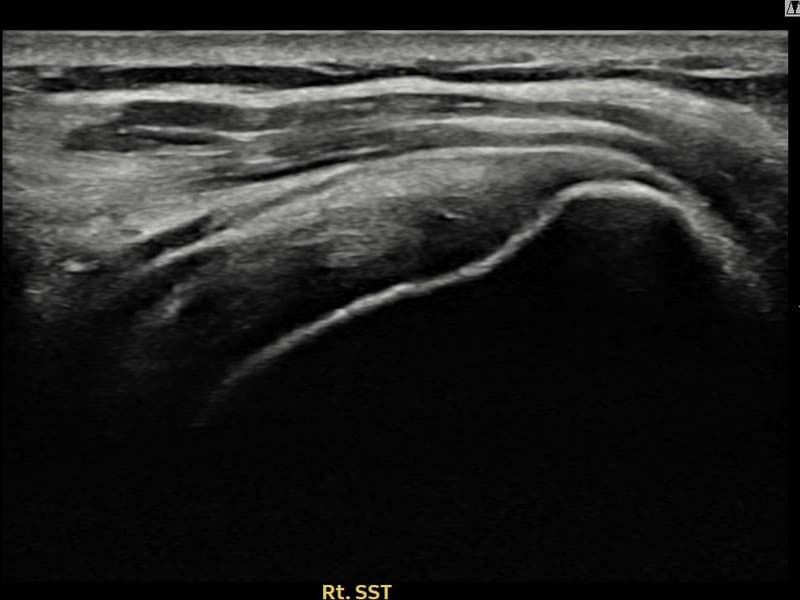

Before

시술 전 초음파 측정 결과 파열 크기는 10mm × 4mm (힘줄 두께의 약 40% 결손)로 확인되었습니다. 시술 전 초음파에서 우측 극상근건 관절면측의 에코 불균질성과 힘줄 내 결손 소견이 확인되었습니다. 시술 후 초음파에서 힘줄 에코 패턴이 균질하게 회복되고 연속성이 정상화된 것이 관찰되었습니다.

60대 여성 환자분으로, 수년간 무릎 통증으로 보행이 불편한 상황에서 어깨까지 아프기 시작하여 일상 전반이 힘들어진 상태였습니다. 초음파 검사에서 우측 극상근건 관절면측의 부분파열이 확인되었으며, 전신 상태와 활동 수준을 고려하여 부담이 적은 비수술 축소봉합술을 선택하였습니다. 시술은 30분 이내에 완료되었고 당일 귀가하셨으며, 보조기 착용 4주 후 천천히 가동 범위를 늘려나갔습니다. 시술 10주 후 추적 초음파에서 극상근건 연속성이 안정적으로 회복된 것이 확인되어 통증 없이 일상 복귀에 성공하셨습니다.